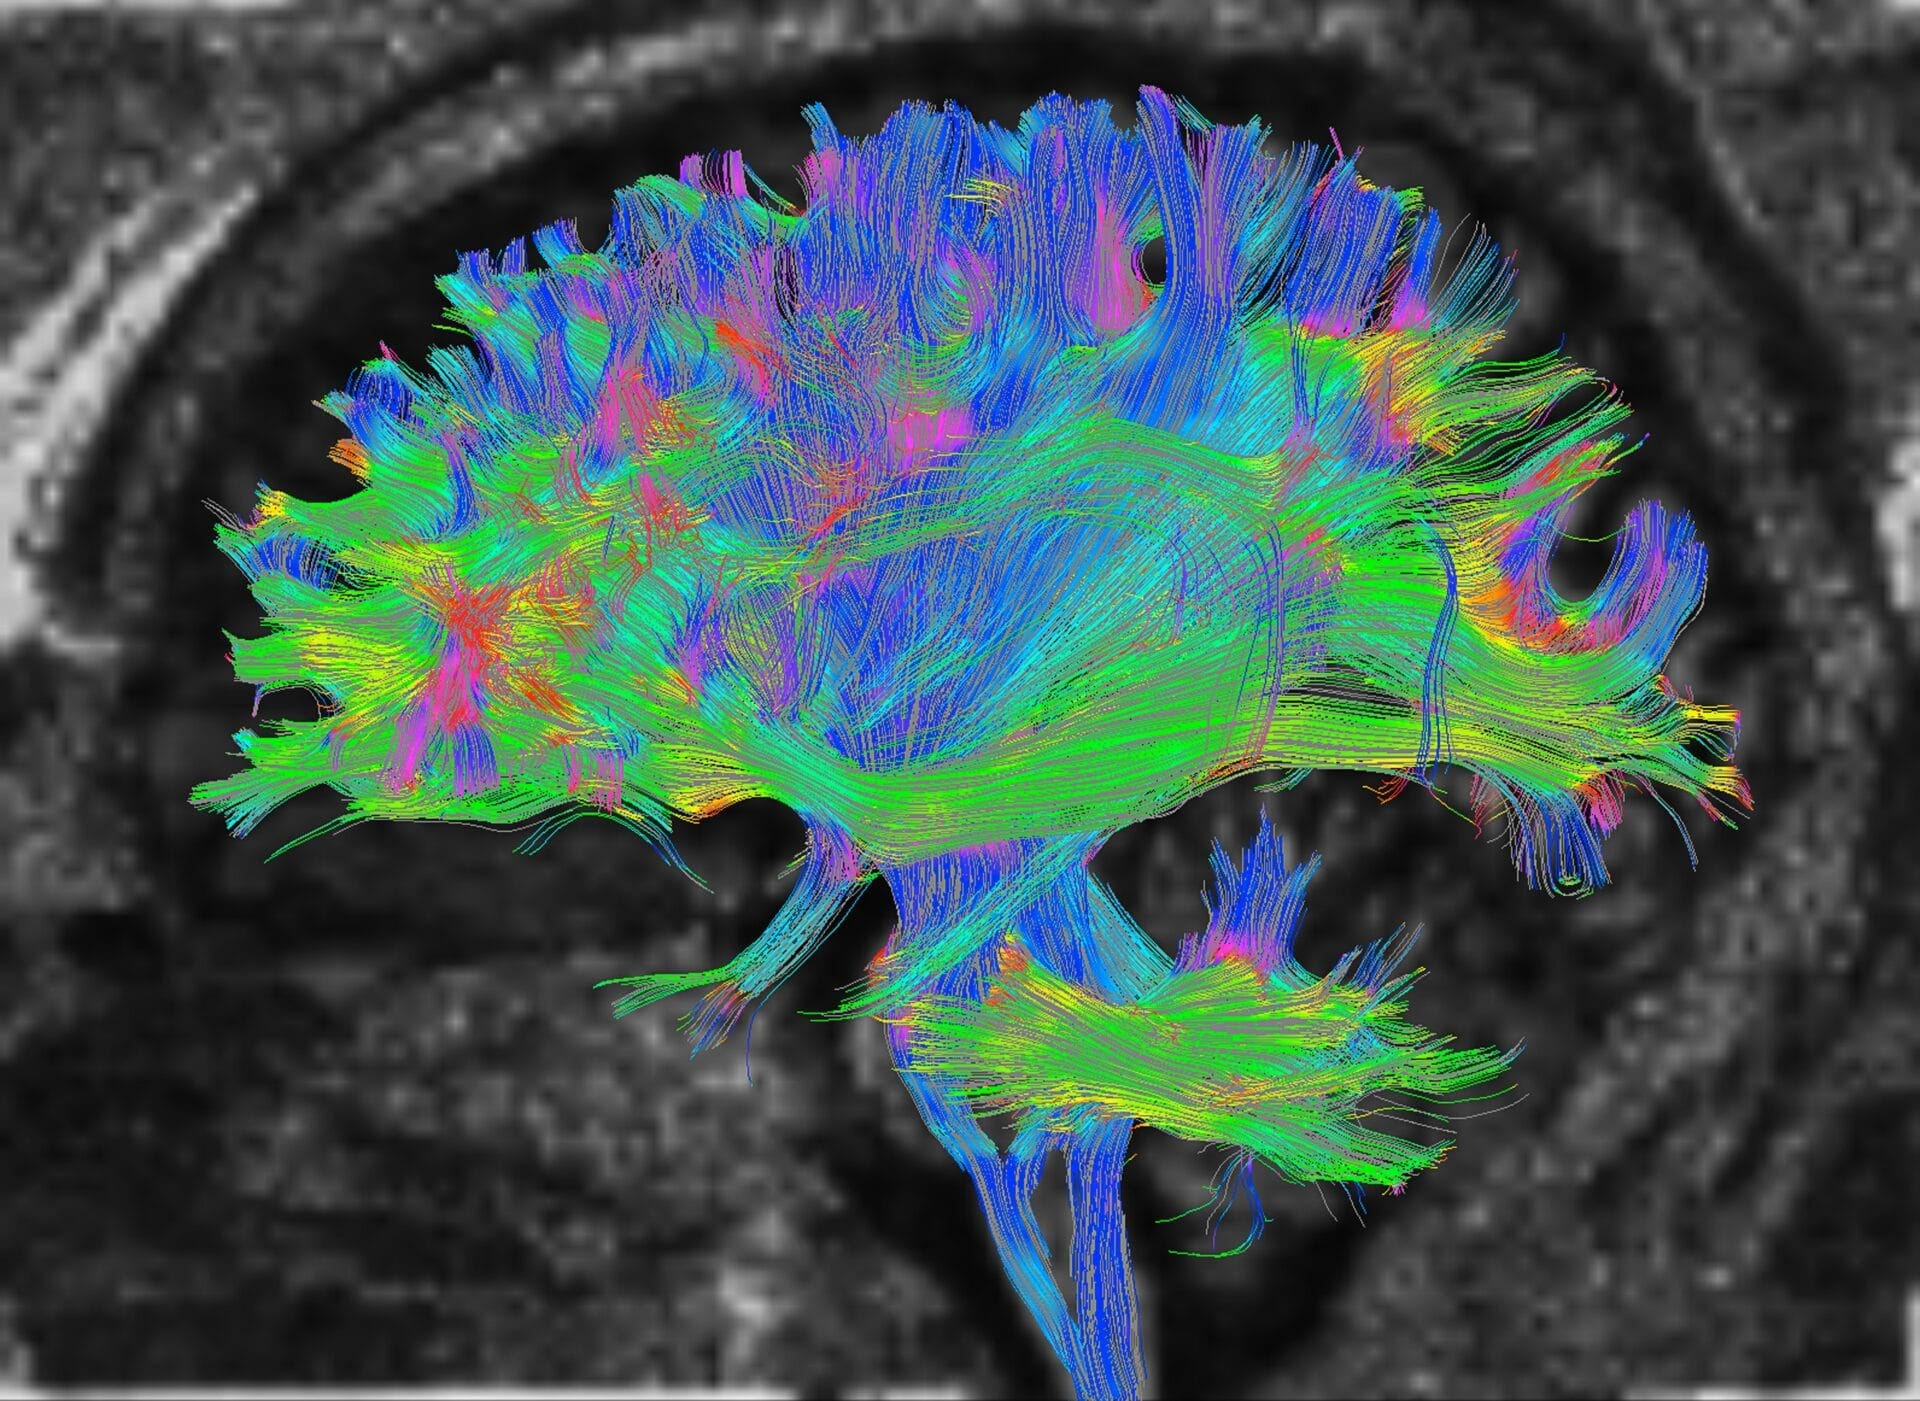

Diffusion Tractography (DTI)

In the context of stroke, DTI offers detailed insights into the integrity of the brain’s white matter tracts, which are crucial for transmitting signals between different brain regions. When a stroke occurs, these pathways can be disrupted, leading to various neurological deficits. DTI helps in visualizing these disruptions, aiding clinicians in assessing the extent of damage caused by the stroke and predicting functional outcomes. By mapping the affected white matter tracts, DTI helps in personalised treatment planning and rehabilitation strategies, ultimately improving the patient’s recovery and quality of life post-stroke.